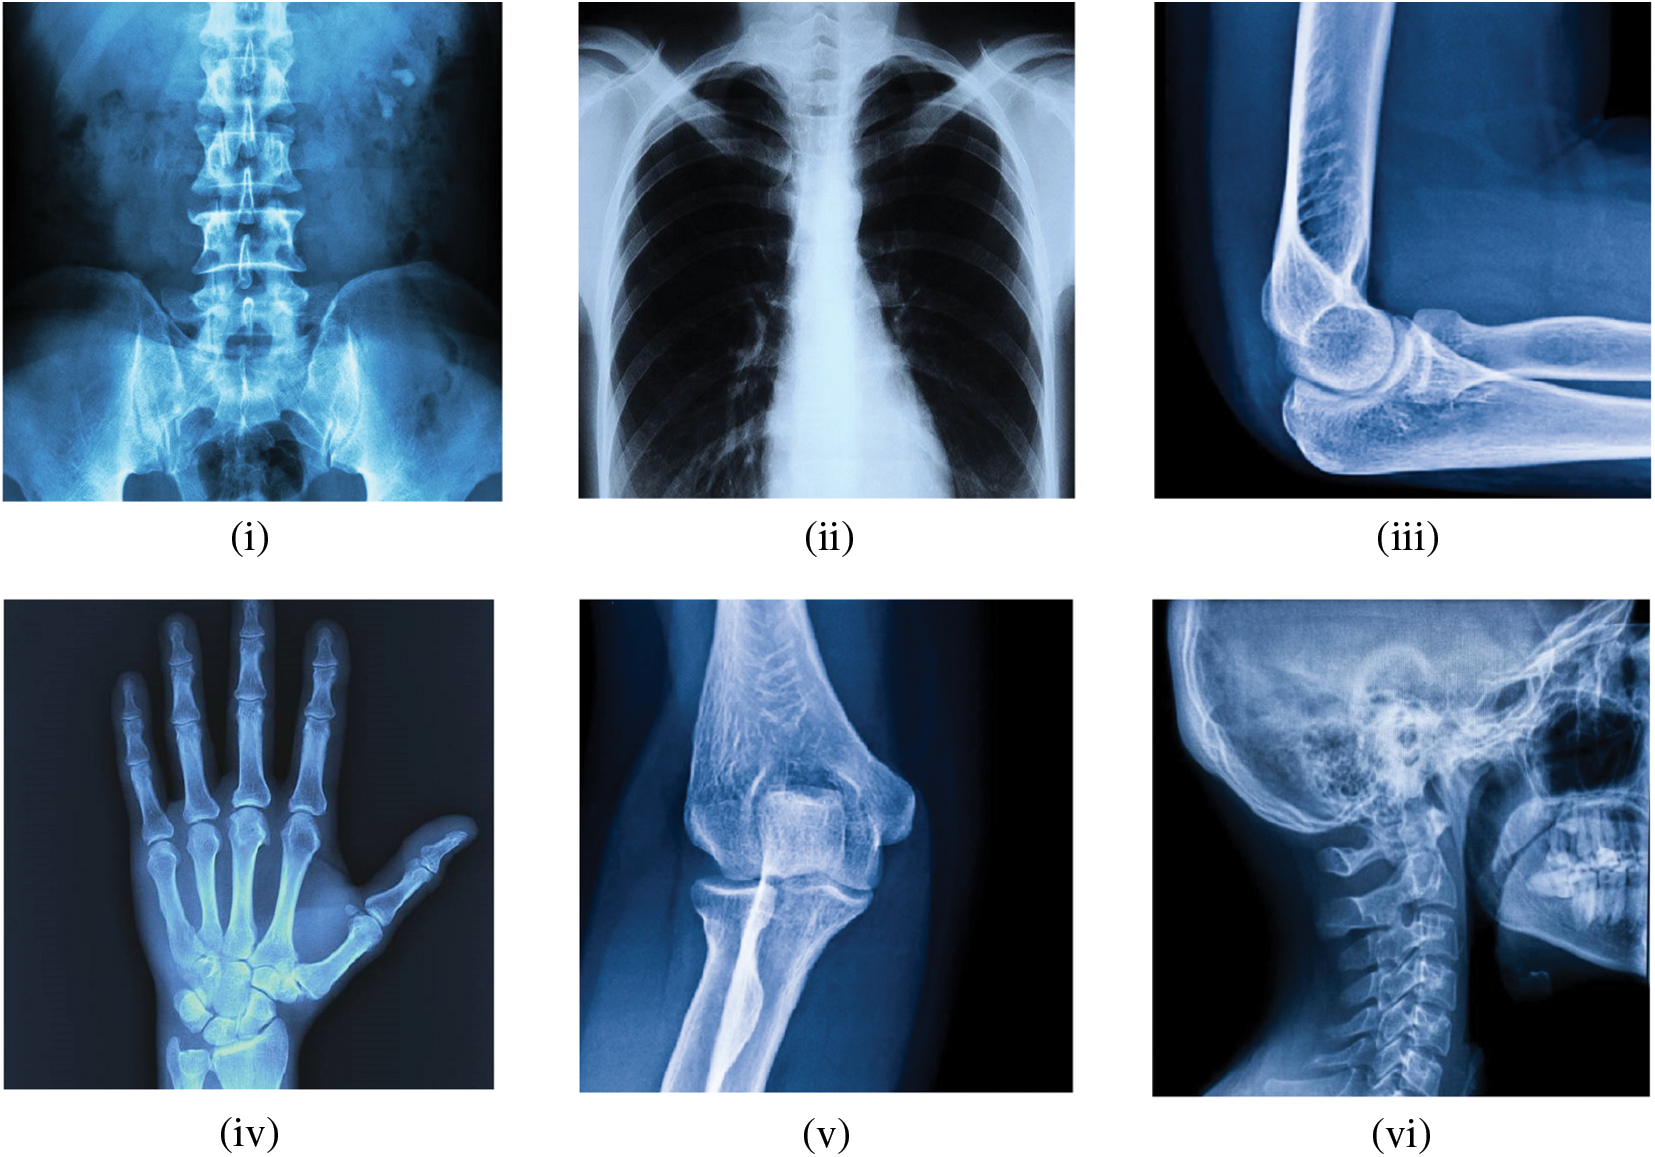

This section details the simulations that were carried out using Matlab 2020a on a 64-bit machine running Microsoft Windows 10 with an Intel(R) Core (TM) i3-3120M CPU running at 2.50 GHz and 8.00 GHZ RAM. The experimental images of the simulation outcomes incorporate abdominal Xray, Chest Xray, elbow Xray, hand Xray, knee Xray, and skull Xray with dimensions

Figure 5: Experimental Xray images (i) Image 1; (ii) Image 2; (iii) Image 3; (iv) Image 4; (v) Image 5; (vi) Image 6